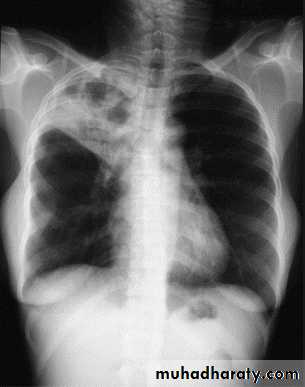

Pleural Effusion on Chest Radiographs.

Posteroanterior (A) and lateral (B) chest radiographs demonstrate the typical meniscoid appearance (arrows) in a patient with a left pleural effusion

Massive pleural effusion with mediastinal shift to the left.

(A) Chest radiograph

(B) CT coronal reconstruction. A massive effusion displaces the mediastinum to the left. CT shows the important pleural effusion together with the enhanced atelectatic left lung.

Note also the depression of the right hemidiaphragm (arrows).